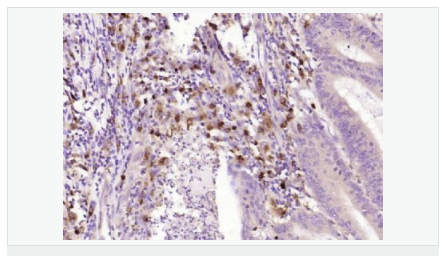

| 產(chǎn)品應(yīng)用 | WB=1:500-2000 ELISA=1:5000-10000 IHC-P=1:100-500 IHC-F=1:100-500 ICC=1:100-500 IF=1:100-500 (石蠟切片需做抗原修復(fù)) not yet tested in other applications. optimal dilutions/concentrations should be determined by the end user. |

| 產(chǎn)品介紹 | This gene encodes an aldo-keto reductase that catalyzes the NADPH-dependent reduction of pteridine derivatives and is important in the biosynthesis of tetrahydrobiopterin (BH4). Mutations in this gene result in DOPA-responsive dystonia due to sepiaterin reductase deficiency. A pseudogene has been identified on chromosome 1. [provided by RefSeq, Jul 2008] Function: Catalyzes the final one or two reductions in tetra-hydrobiopterin biosynthesis to form 5,6,7,8-tetrahydrobiopterin. Subunit: Homodimer. Subcellular Location: Cytoplasm. Post-translational modifications: In vitro phosphorylation of Ser-213 by CaMK2 does not change kinetic parameters. DISEASE: Defects in SPR are the cause of dystonia DOPA-responsive due to sepiapterin reductase deficiency (DRDSPRD) [MIM:612716]. In the majority of cases, patients manifest progressive psychomotor retardation, dystonia and spasticity. Cognitive anomalies are also often present. The disease is due to severe dopamine and serotonin deficiencies in the central nervous system caused by a defect in BH4 synthesis. Dystonia is defined by the presence of sustained involuntary muscle contractions, often leading to abnormal postures. Similarity: Belongs to the sepiapterin reductase family. SWISS: P35270 Gene ID: 6697 Database links: Entrez Gene: 6697 Human Omim: 182125 Human SwissProt: P35270 Human Unigene: 301540 Human Important Note: This product as supplied is intended for research use only, not for use in human, therapeutic or diagnostic applications. |